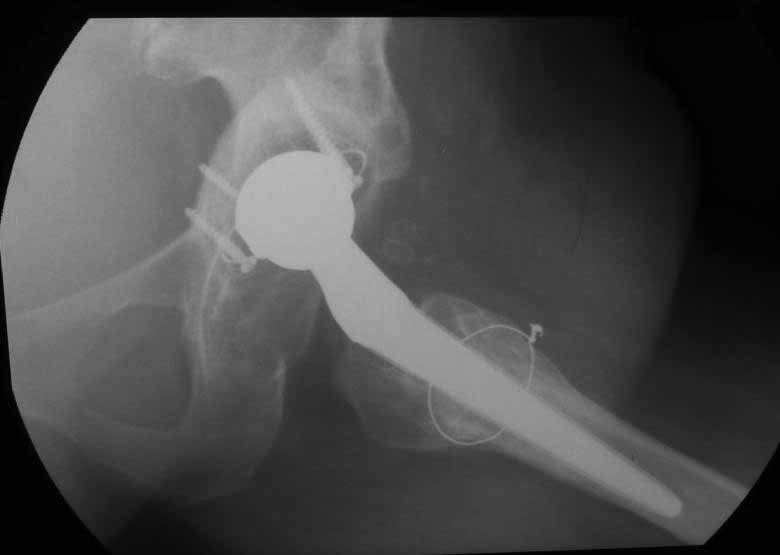

Уважаемые коллеги. Хотелось бы услышать мнения и советы по представляемому случаю. Пациентка 45 лет. Бесцементное эндопротезирование левого тазобедренного сустава 6 лет назад (впадина RM, Mathys, металл-металл, ножка Зульцеровская). За 10 лет до протезирования – коррегирующая остеотомия бедренной кости, которая не срослась в течение года до удаления пластины, а затем срослась в течение 3 месяцев иммобилизации в кокситной повязке. После протезирования получилось наблюдать пациентку почти постоянно, поскольку через 2 года синтезировал ей лодыжки на оперированной стороне, затем, через несколько месяцев удалил фиксаторы, а в 2009г. резецировал мениск на противоположной стороне. Боли все эти годы не беспокоили. Пациентка чуть выше среднего роста, вес тела нормальный. Физические нагрузки переносила хорошо. Работает на 7 этаже без лифта. Год назад экстирпация матки по поводу лейомиомы больших размеров. Несколько месяцев назад появились боли в области левого тазобедренного сустава. При рентгеновском и КТ исследованиях (июль с.г.) – нестабильность тазового компонента. От предложенной замены протеза пациентка на тот момент, слава богу, отказалась. Через какое то время боли в области левого тазобедренного сустава практически полностью прошли, а около 2 месяцев назад появилось ощущение патологической подвижности таза и боли в паху справа, которые через некоторое время уменьшились, а потом снова усилились после значительных физических нагрузок (много ходила по песку на пляже, носила тяжести). Ежедневно принимала диклофенак. На рентгенограммах – переломы правой лонной кости. Сейчас госпитализирована из-за болей в паху справа. Боли слева не беспокоят. На фоне снижения нагрузок в стационаре боли значимо уменьшились. Способна ходить без средств дополнительной опоры.В анализах крови чуть повышены трансаминазы и гамма-ГТ, моча без особенностей.

Вопросы: -правильно ли я расцениваю переломы как стрессовые на фоне неполноценного таза (pelvic insufficiency stress fractures)? -Можно ли так же расценить ситуацию на стороне протеза и, соответственно, не торопиться с ревизией, рассчитывая на вторичную стабилизацию? Уж больно не хочется менять ножку. -Если думать о ревизии, то когда? На представленных снимках тазобедренный сустав до и сразу после операции, затем 2 снимка 2009г., когда ничего не беспокоило, затем КТ 2-х месячной давности и вчерашние рентгенограммы обоих тазобедренных суставов.

Если внимательно посмотреть на рентгеновские снимки, то видно, что пара трения действительно металл-металл.